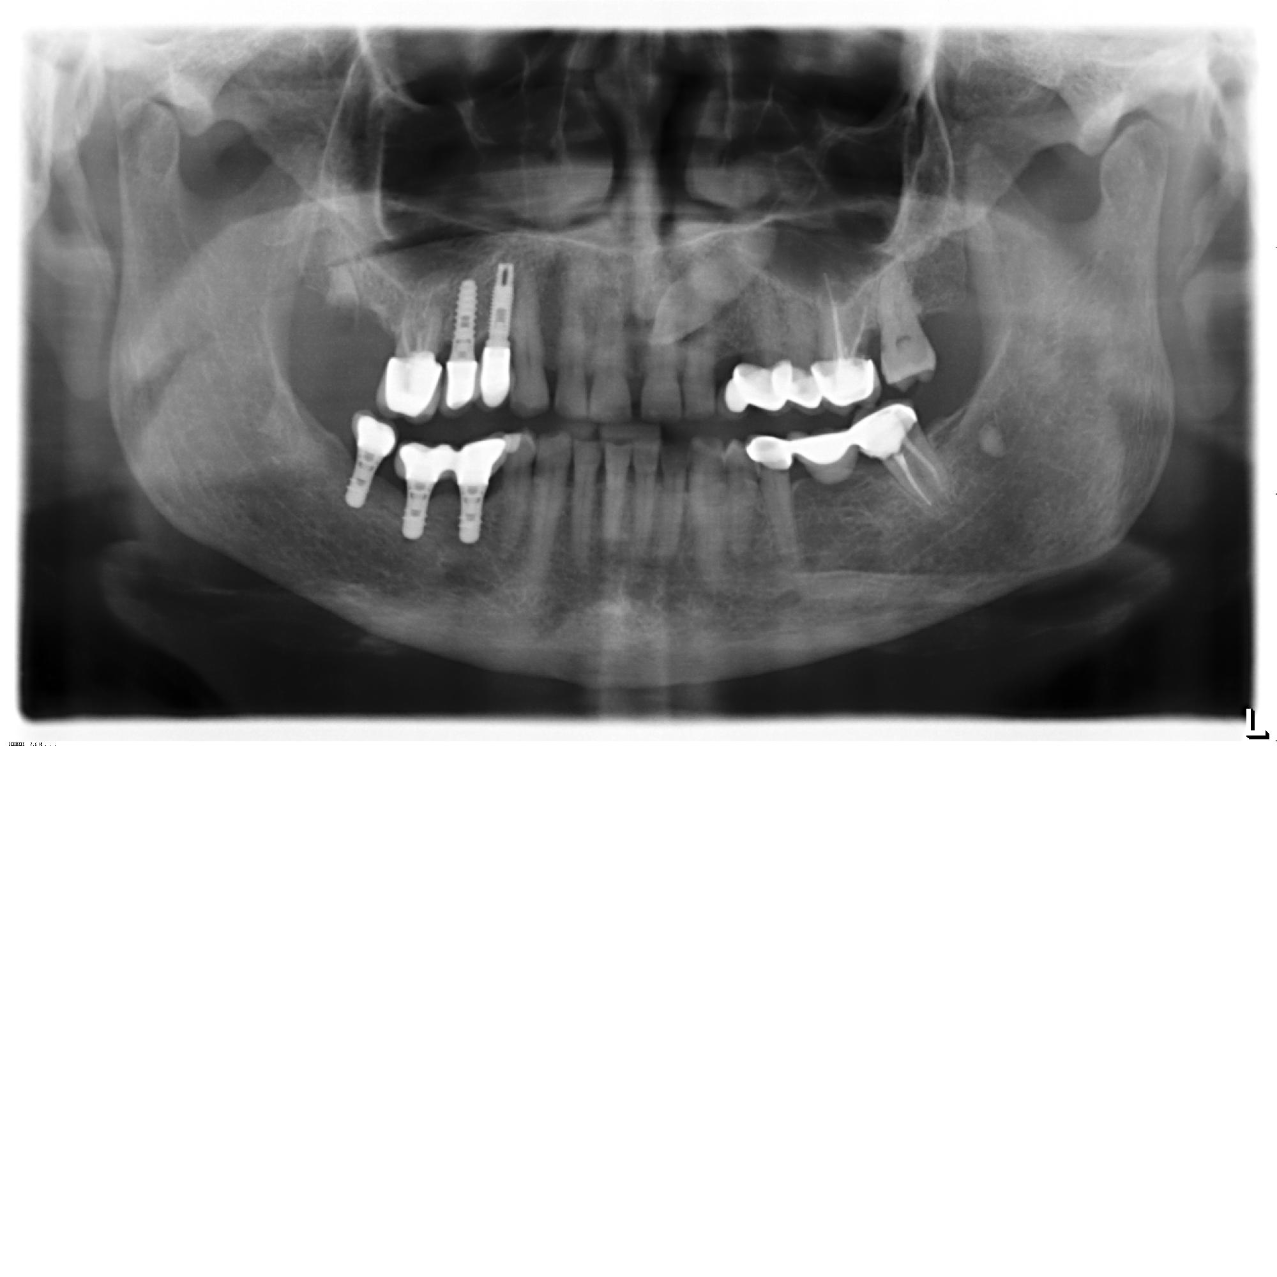

Buenos días, necesitamos saber que implantes son 45,46,47.

Con implantes Straumann Tissue Level, y diría que plataforma RN (4,8). Necesitáis un destornillador torx. Los tres llevan pilares octa. Si son para atornillar, te vale también el mismo destornillador (se mete en el interior de la rosca del tornillo protésico del pilar).